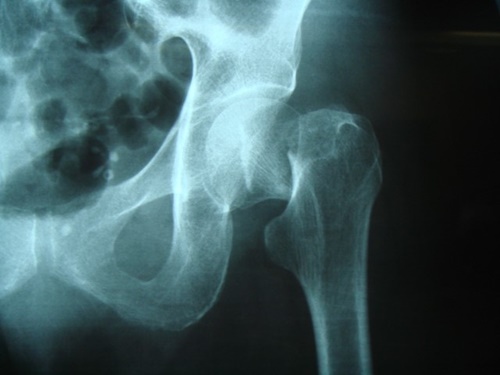

ภาพกระดูกปกติ

ภาพกระดูกพรุน